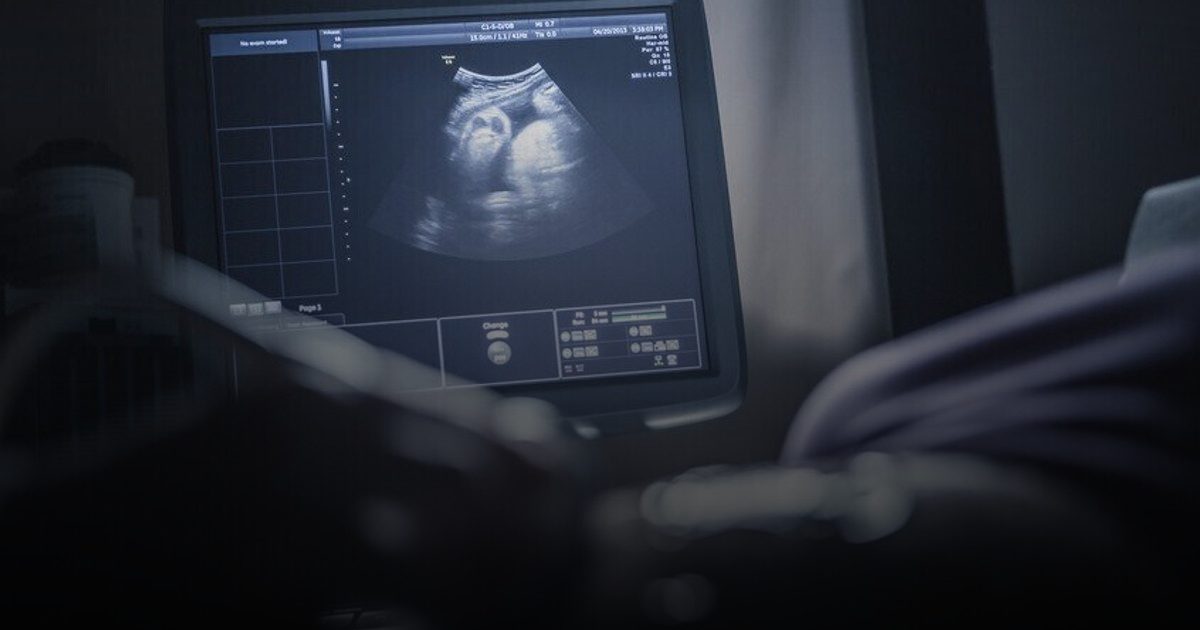

كبسولة الصحية – نيوز ميديكال كشف علماء في أبحاث الخصوبة عن اكتشاف مهم، حيث أشاروا إلى أن تقدم عمر المرأة هو العامل الأساسي والمباشر وراء توقف تطور الأجنة، وهذا التأثير يحدث بشكل مستقل عن مشاكل الكروموسومات التي ظلت لسنوات طويلة تعد السبب الرئيسي وراء فشل عملية التطور الجنيني. شملت هذه الدراسة، التي